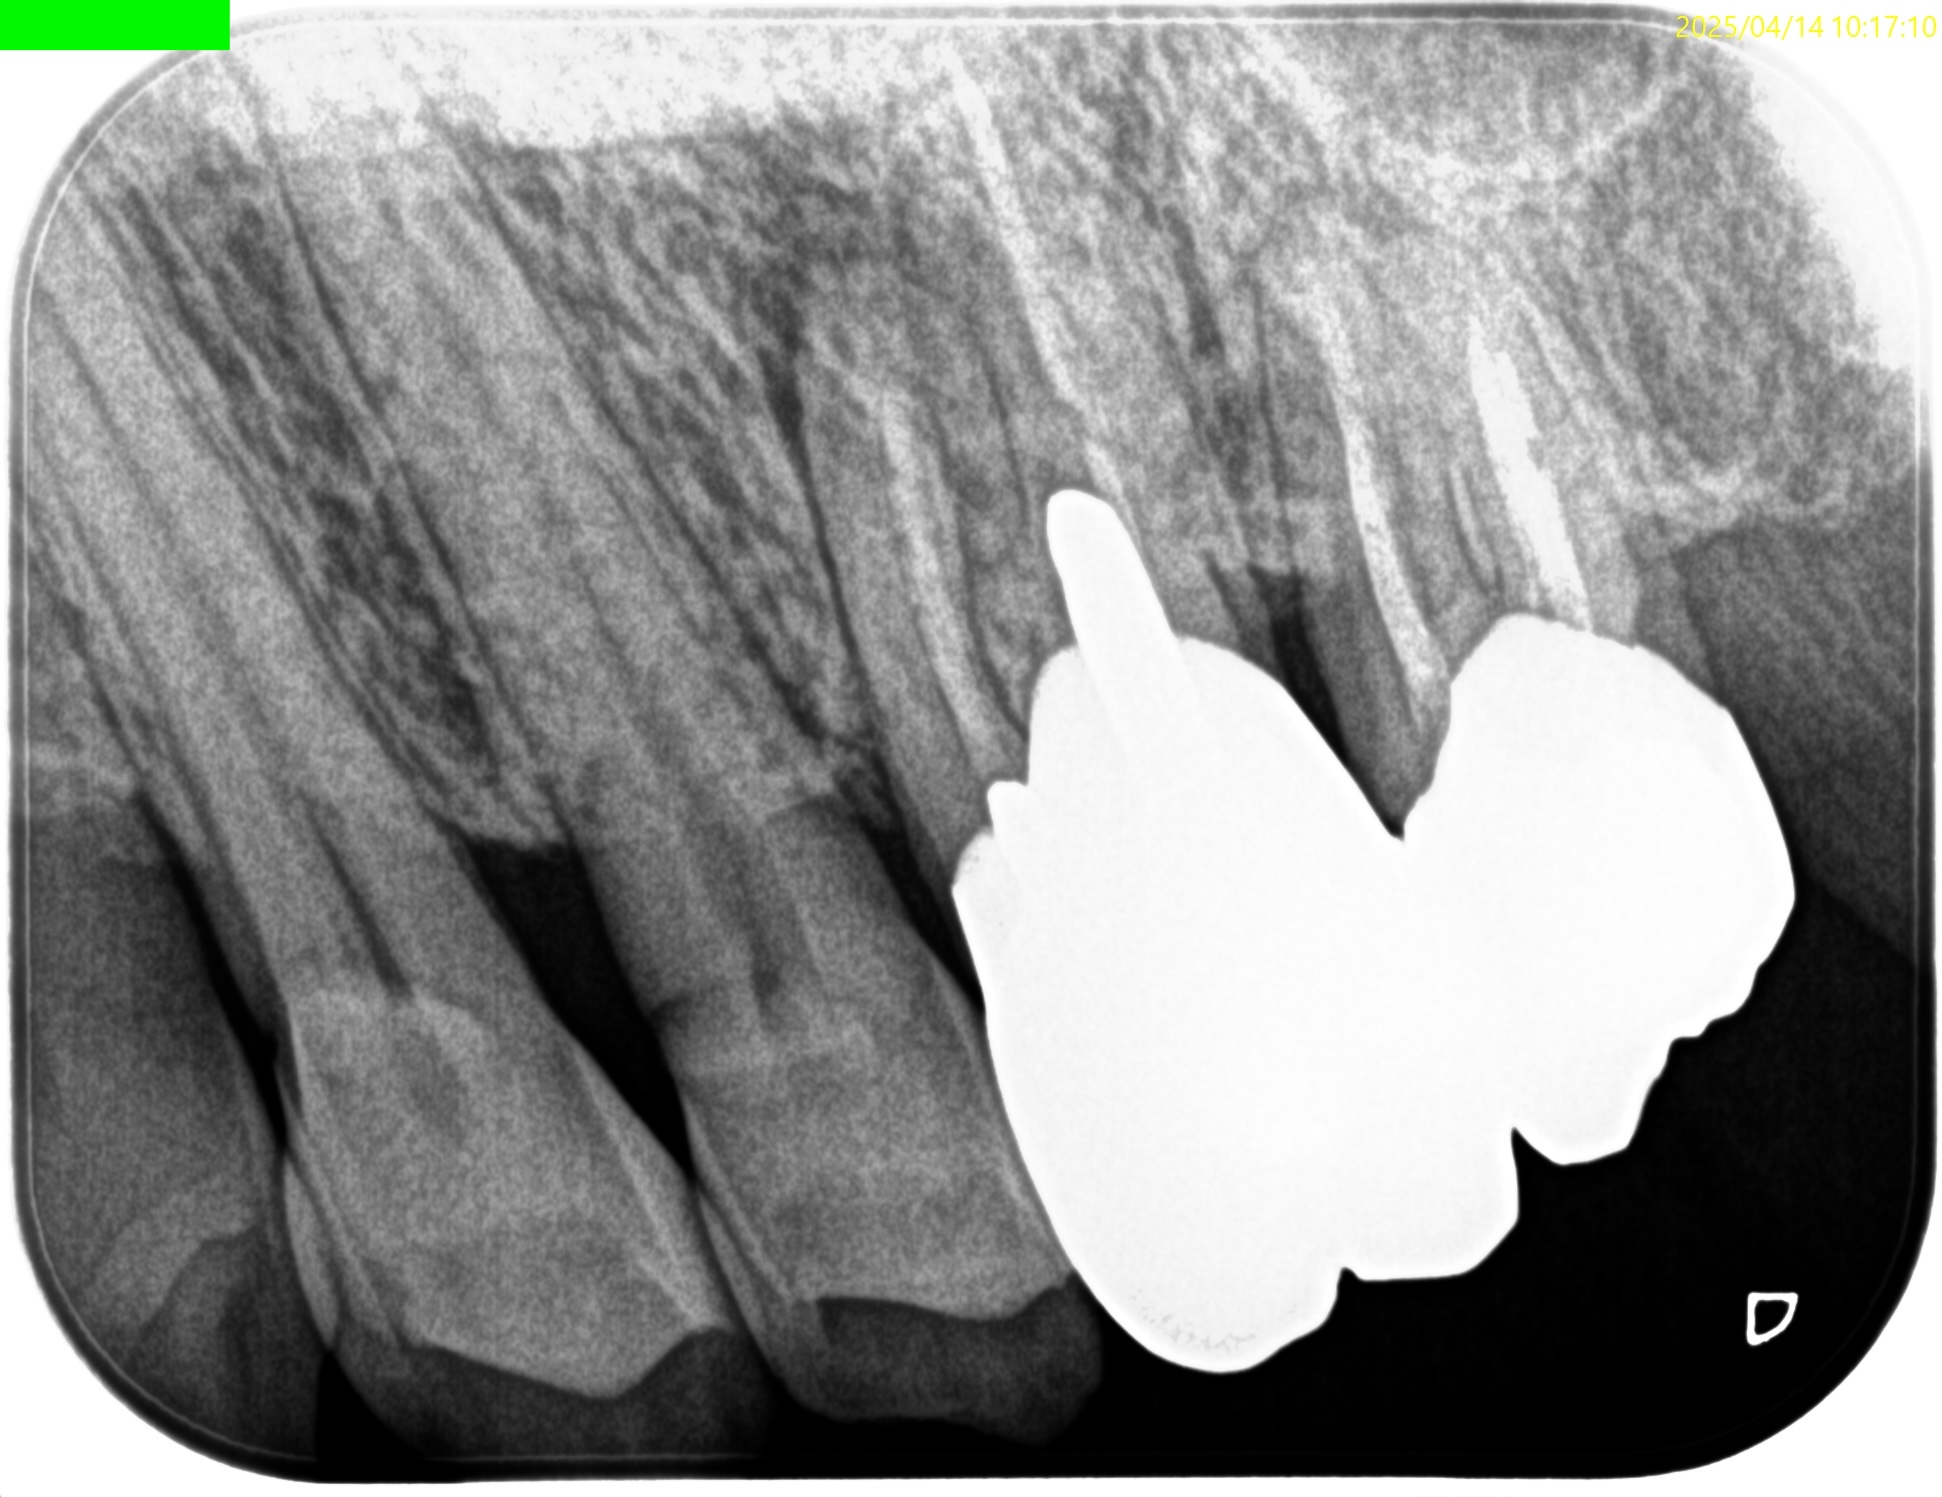

その際は、

DBを巻き込まないようにApicoectomyすべきではあるが、

たとえDBの歯根を傷つけても臨床的には問題にならないだろう。

DB

P

Pulp Dx: Previously treated

Periapical Dx: Chronic apical abscess

Recommended Tx: Apicoectomy